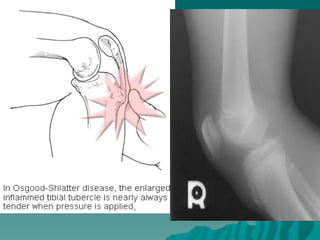

Osgood-Schlatter Hastalığı:  Tüberasitastibianın osteokondrozudur. Hastalığın, tüberositas tibiaya kuadriseps kasıyla gelen tekrarlayıcı kuvvetler sonucu geliştiği düşünülür.  Erkeklerde ve adolesan çağda daha sıktır. Bilateral olabilir. Dizin ön tarafında ağrı olur. Yakınmalar koşma, zıplama, merdiven çıkma ile artar, Dinlenmekle geçer.  Muayenede tüberasitas tibia genişlemiş ve duyarlıdır.

Osgood-Schlatter Hastalığı:

 Tüberasitas tibianın osteokondrozudur.

Hastalığın, tüberositas tibiaya kuadriseps

kasıyla gelen tekrarlayıcı kuvvetler

sonucu geliştiği düşünülür.

 Erkeklerde ve adolesan çağda daha sıktır.

Bilateral olabilir. Dizin ön tarafında ağrı

olur. Yakınmalar koşma, zıplama,

merdiven çıkma ile artar, Dinlenmekle

geçer.

 Muayenede tüberasitas tibia genişlemiş ve

duyarlıdır.